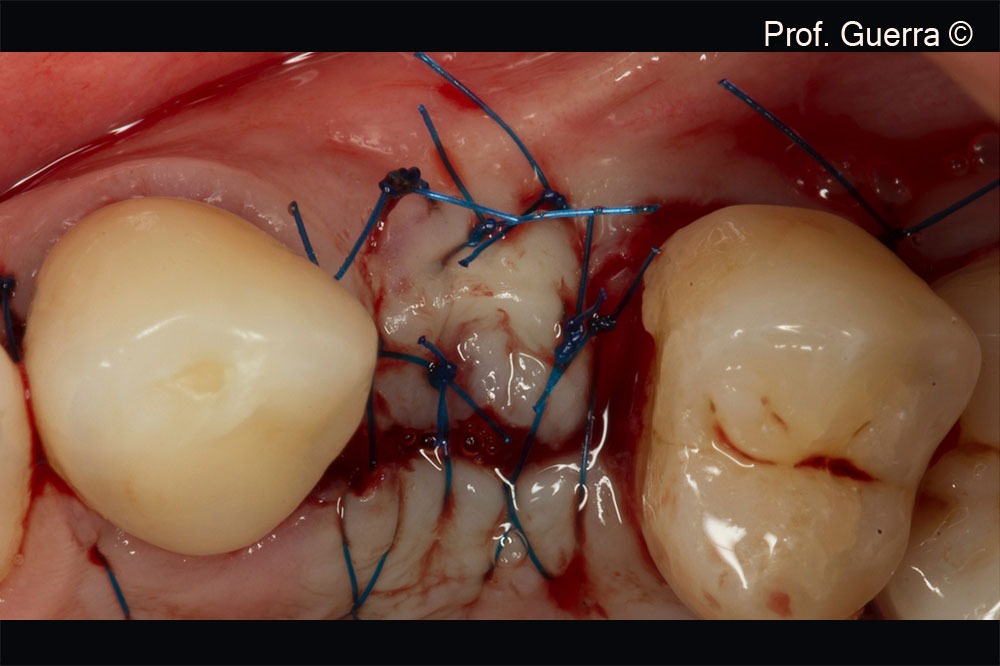

Left and Middle) horizontal mattress sutures (tension-free) mesially and distally; Right) interrupted suture in the papilla base between 22 and 23

Suture final aspect